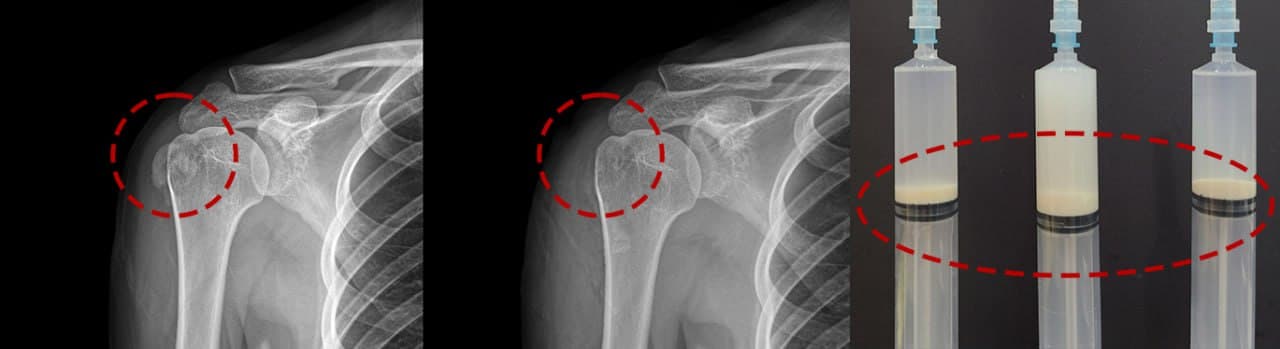

1회 시술 전·후 비교

좌: 시술 전 (선명한 석회 덩어리) | 우: 1회 시술 후 (완전 소실)

시술 전후 X-ray — 실제 케이스

단단한 석회도 1회 시술 후 완전 제거. 실제 환자 X-ray입니다.

케이스 1 — 시술 전·후

케이스 2 — 시술 전·후

케이스 3 — 시술 전·후